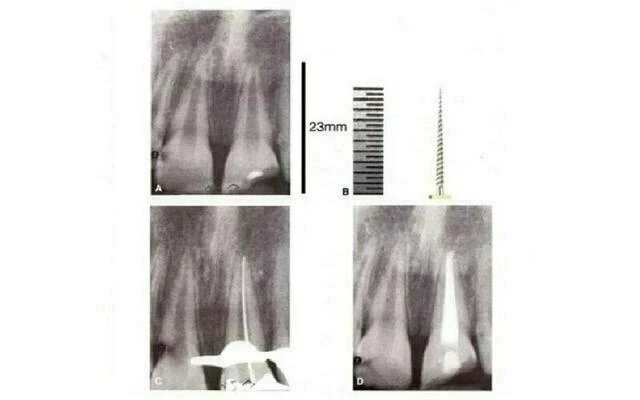

Hình 2.1. A. Hình ảnh X-quang răng cửa giữa dưới theo chiều ngoài trong. B. Xoang mở tủy chưa đủ rộng. C. Một trâm số #8 đi vào ống ngoài gặp trở ngại ở phần cổ răng. Do phần gờ ngà bên trong nên dụng cụ bị cản lại khi đi vào ống trong. D. Dùng mũi khoan tròn với tay khoan chậm loại bỏ hoàn toàn phần gờ ngà này. E. X-quang của xoang tủy khi hoàn thành. F. Trâm số #8 có thể vào ống trong dễ dàng. G. Hai dụng cụ đi vào cho thấy có hai ống tủy với 1 lỗ chóp chung.